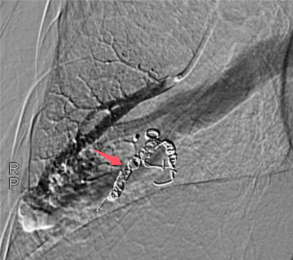

近日,重庆医科大学附属璧山医院(重庆市璧山区人民医院)呼吸与危重症医学科血管介入团队成功完成了一项具有里程碑意义的手术——选择性肺动脉栓塞术,为一名肺动静脉瘘患者带来了新生。这一手术的成功实施标志着我院在肺血管介入领域达到了新的高度。